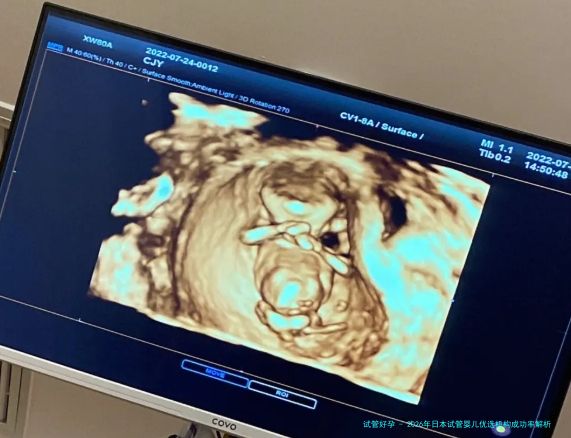

跟着科技的发展,试管婴儿技术已然成为不孕不育家庭解决生育问题的有效路径。近些年来,日本试管婴儿技术在全球范围内备受注意,其成功率及服务质量都得到了广泛的承认。本文将给您剖析2026年日本试管婴儿优先选择机形成功率,并提供前往日本费用一览。

2026年日本试管婴儿优选机构成功率解析

在日本,试管婴儿技术经非常多年的发展,已然达到了国际前沿水平。根据2026年的统计数据,日本试管婴儿优先选择机形成功率普遍较高。以下是几家具有代表性的机形成功率解析: